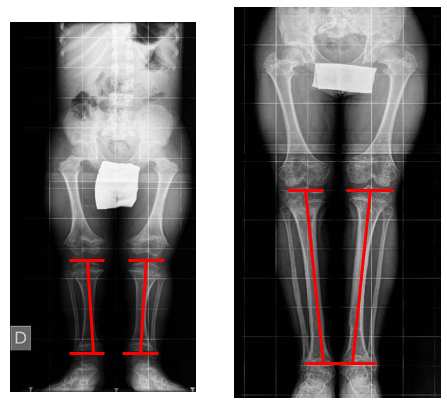

d) Tibial angulation (Figure 4), calculated by comparing the orientation of the joint lines of the knee and ankle on preoperative radiographs with those on the postoperative radiographs [11,13].

Figure 4: Medial Proximal Tibial Angle in a Preoperative and Postoperative Radiograph with 15cm Tibial Lengthening